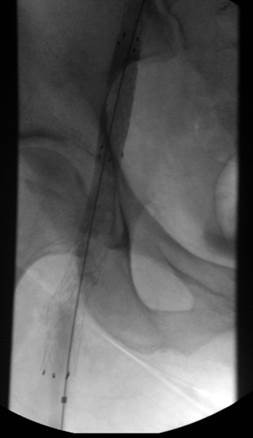

Venograma en posición de decúbito prono de la rama ilíaca izquierda que indica una estenosis causada por el tumor que comprime la uretra y la vena ilíaca externa izquierda.